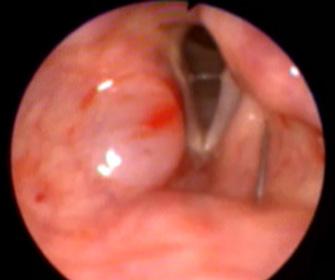

Injectările de augmentare/ medializare de coardă vocală Cele mai frecvente materiale de augmentare care pretează injectărilor ambulatorii includ:

• Acidul hialuronic (AH): biodegradabil, utilizat pentru augmentări temporare (3–9 luni), ideal în paralizia vocală recent instalată sau testare terapeutică;

• Hidroxiapatita de calciu (CaHA): material semipermanent (1–2 ani), indicat în paralizii stabile, presbifonie, atrofie vocală.

Indicații: Paralizie unilaterală de coardă vocală, presbifonie, atrofii și incompetență glotică, testare terapeutică înaintea tiroplastiei.

Se practică sub control fibroscopic și există mai multe variante de abord, fiecare metodă având avantaje și dezavantaje. În viziunea autorului, acestea sunt:

• prin canalul de lucru al fibroscopului (Fig. 2). Avantaj: cel mai ușor tolerabil de către pacient; dezavantaje: pretează doar pentru AH, nu și pentru CaHA care este prea vâscos;

• transoral (Fig. 3). Avantaje: vizualizare optimă a versantului superior al corzilor vocale; se poate aplica pacienților

aflați în tratament anticoagulant oral fără ca aceștia să-l întrerupă; dezavantaje: este cel mai puțin tolerabil; se pierd aproximativ 0,6 ml de substanță în spațiul mort al acului;